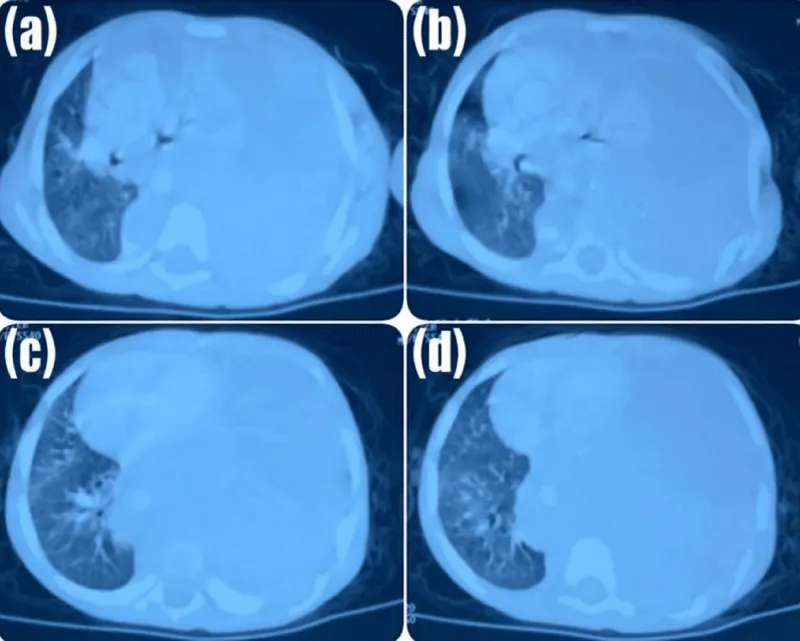

A chest radiograph performed in January 2024 demonstrated a large homogeneous opacity occupying the left hemithorax with mediastinal shift toward the contralateral side (Figure 1).

Figure 1: Chest Radiograph at Initial Presentation.

Chest radiograph demonstrating a large homogeneous left-sided thoracic opacity associated with mediastinal shift to the contralateral side, initially suggestive of pulmonary infection.